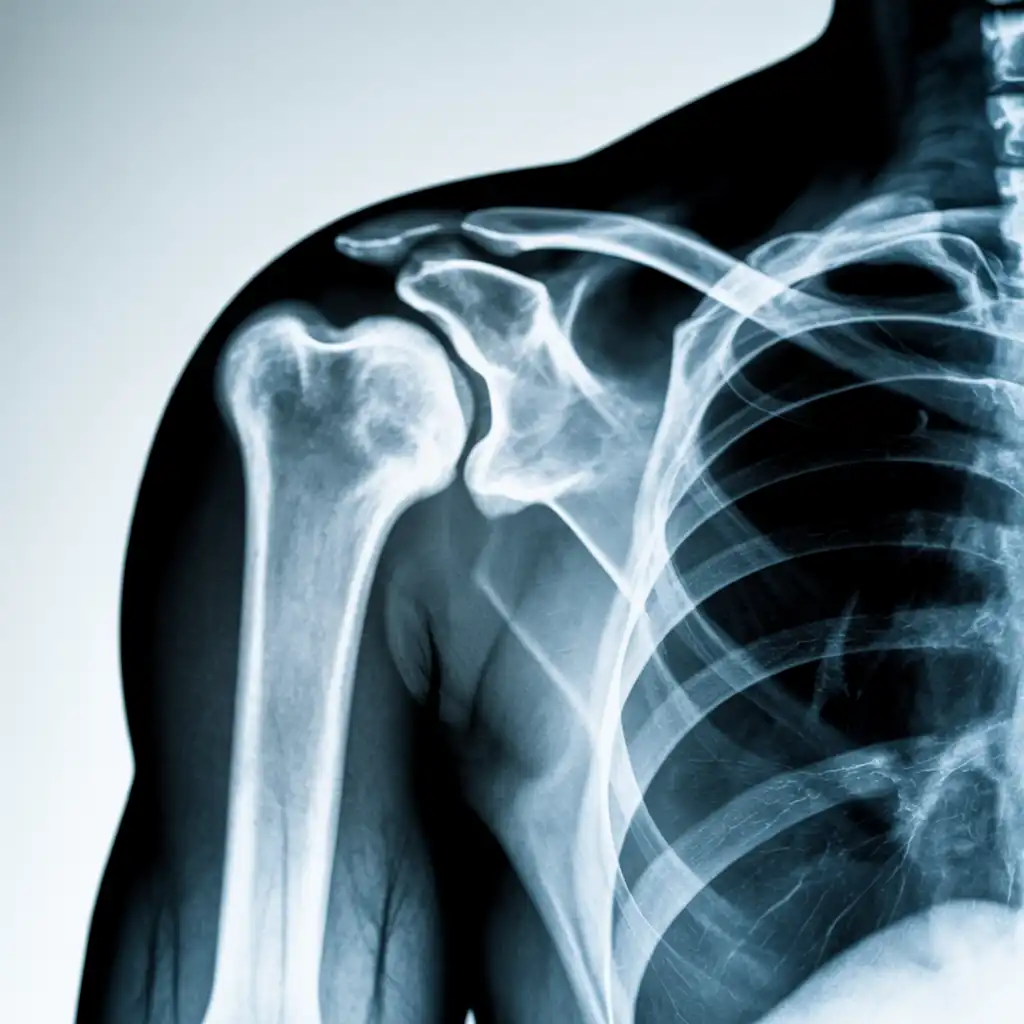

Una radiografia a domicilio è un esame radiologico eseguito da un tecnico specializzato che viene a casa tua con apparecchiature digitali portatili. L’esame si svolge sul posto, senza spostare il paziente e con la stessa qualità di una struttura ospedaliera.

Dopo l’acquisizione delle immagini, queste vengono inviate al medico radiologo che referta rapidamente e ti invia tutto in formato digitale. Un servizio comodo, sicuro e ideale per chi ha difficoltà negli spostamenti.